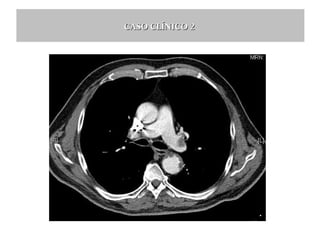

CASO CLÍNICO 2

Gasometría arterial basal:

pH: 7.460 (7.350 - 7.450 )

pCO2: 31 mmHg (35 - 48 )

pO2: 70 mmHg (83 – 108)

Bicarbonato: 21.5 mmol/L (22 - 26 )

SBC (Bicarbonato estándar) : 23.8 mmol/L

TCO2: 22.5 mmol/L

ABE (Exceso de base actual) : -2.5 mmol/L (-2 – 2)

SBE (Exceso de base estándar) : -1.2 mmol/L

sO2 : 96.5 % (94.00 - 98.00 )

Alcalosis respiratoria aguda:

- ↓ PCO2

- ↓ 10 mmHg PCO2 debe ↓ 2 mEq HCO3-

Caso clínico:

pH: 7.46

pCO2: 31 mmHg

pO2: 70 mmHg

Bicarbonato: 21.8 mmol/L

1 x 2 = 2 mEq debería disminuir el HCO324 (c.n) -2 = 22